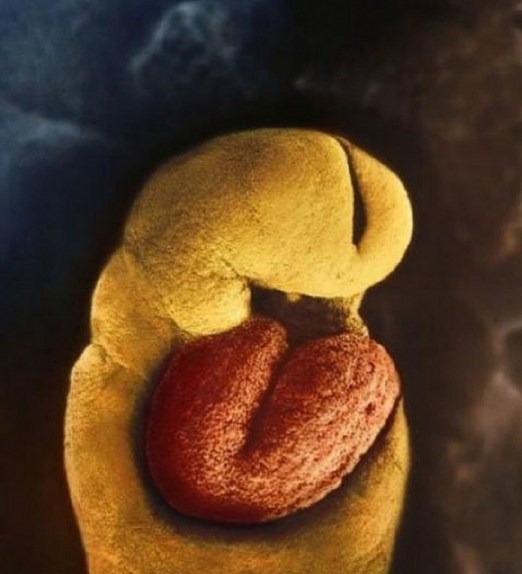

Ембрионът на 22 дни. Сивата зона ще се превърне в мозъка на детето.

До 18-ия ден от развитието, сърцето на зародиша започва да бие.

28 дни след оплождането.